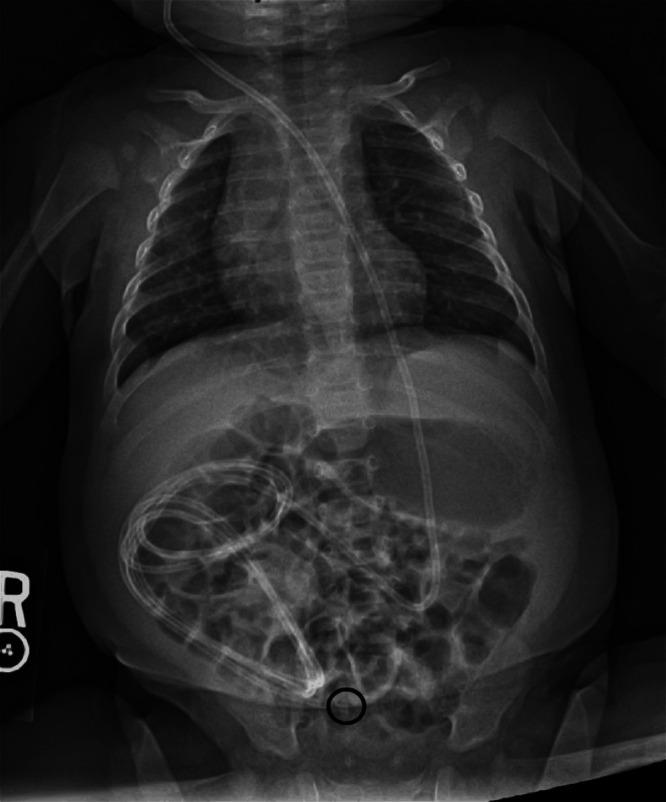

When ventriculoperitoneal (VP) shunts and umbilical hernias coexist in the same patient, unique complications can occur. Typically, these are readily identified problems such as cerebrospinal fluid (CSF) fistulas or entrapment of the peritoneal catheter in the hernia. The authors present cases of two children whose VP shunt dysfunction resolved after repair of their umbilical hernias.

OBSERVATIONS

The authors present two cases of infant patients with shunted hydrocephalus and umbilical hernias. In both cases, the patients presented with distal shunt malfunctions not due to infection. Their shunt function improved once the umbilical hernia was repaired by pediatric surgery. Neither has required shunt revision since umbilical hernia repair.

Although there are case reports of VP shunts eroding through the umbilicus, developing CSF fistulas, or becoming trapped inside umbilical hernias, there is no case of VP shunt dysfunction caused by just the presence of an umbilical hernia. The authors suspect that the catheter may intermittently enter and exit the hernia. This may cause intermittent obstruction of the distal catheter, or inflammation in the hernia may occur that limits CSF absorption.